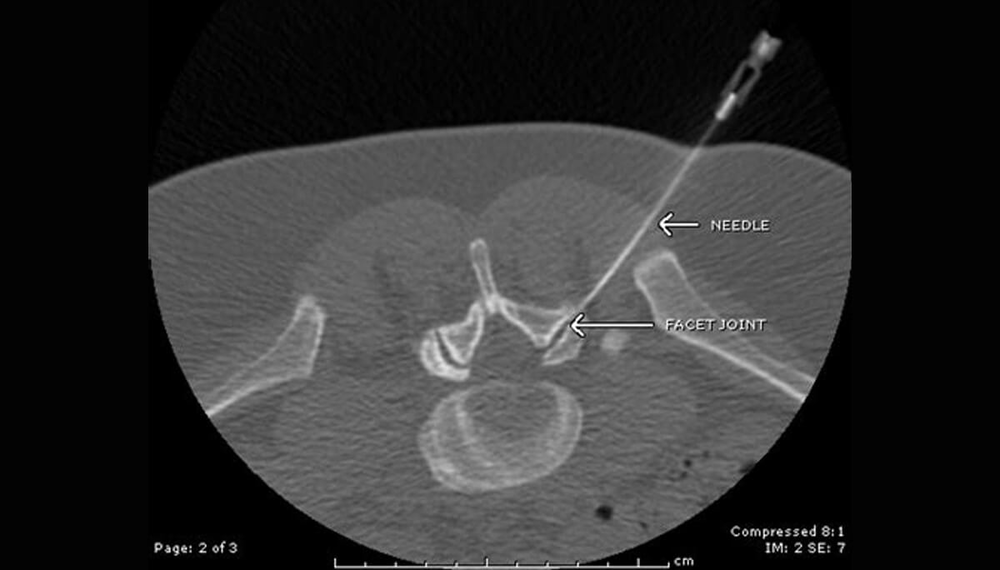

La réalisation de la procédure au scanner permet d’avoir un contrôle précis du bon positionnement de l’aiguille et de permettre une reproductibilité du geste.

On utilise deux types d’abord : une voie foraminale péri radiculaire (à l’étage cervical et lombaire) pour les hernies latérales et une voie épidurale (utilisée uniquement à l’étage lombaire) pour la hernie médiane et le canal lombaire étroit.